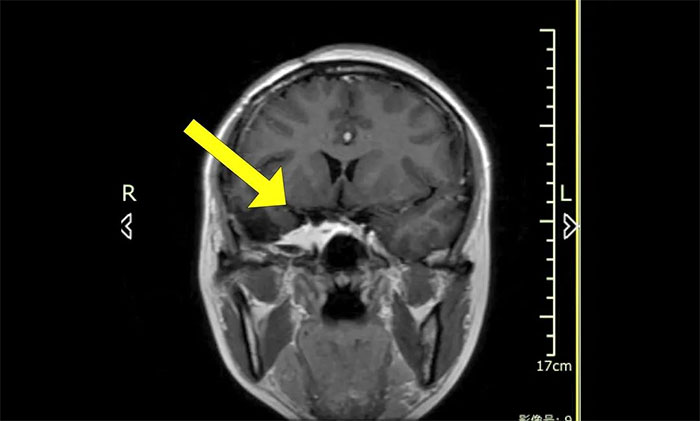

陳琦主任團(tuán)隊(duì)根據(jù)患者病情,精心設(shè)計(jì)了分期治療的靶區(qū)和治療劑量,用伽瑪射線聚焦于病灶,使病變組織凋亡并逐漸阻斷血供,從而達(dá)到治療目的。完成治療后患者順利出院,半年后來院復(fù)查,病灶較前明顯縮小。

▲ 治療后病灶明顯縮小